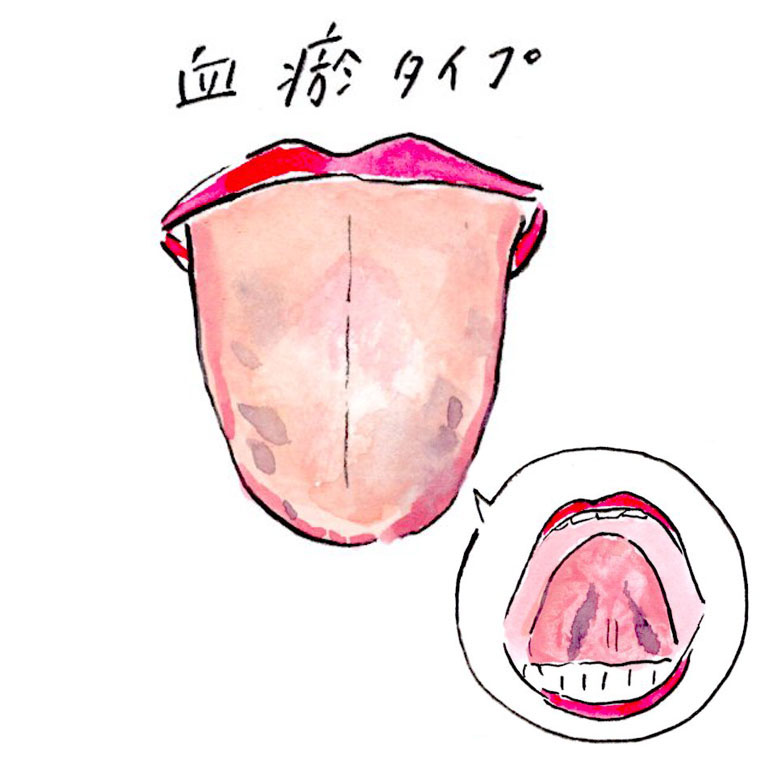

舌にひび割れがある」ときの体質・体調 - 漢方ライフ- 漢方を始めると、暮らしが変わる。

白い、ガタガタ、ひび割れ 。“舌”でわかる体調不良のサインとは?田中友也さん 季節の養生法からだにいいこと。

舌のサイン 院長ブログ八尾市のオカモト鍼灸整骨院。

舌診~毎日鏡の前で健康チェックをしたくなる舌の状態を解説 祥泉針灸整骨院。